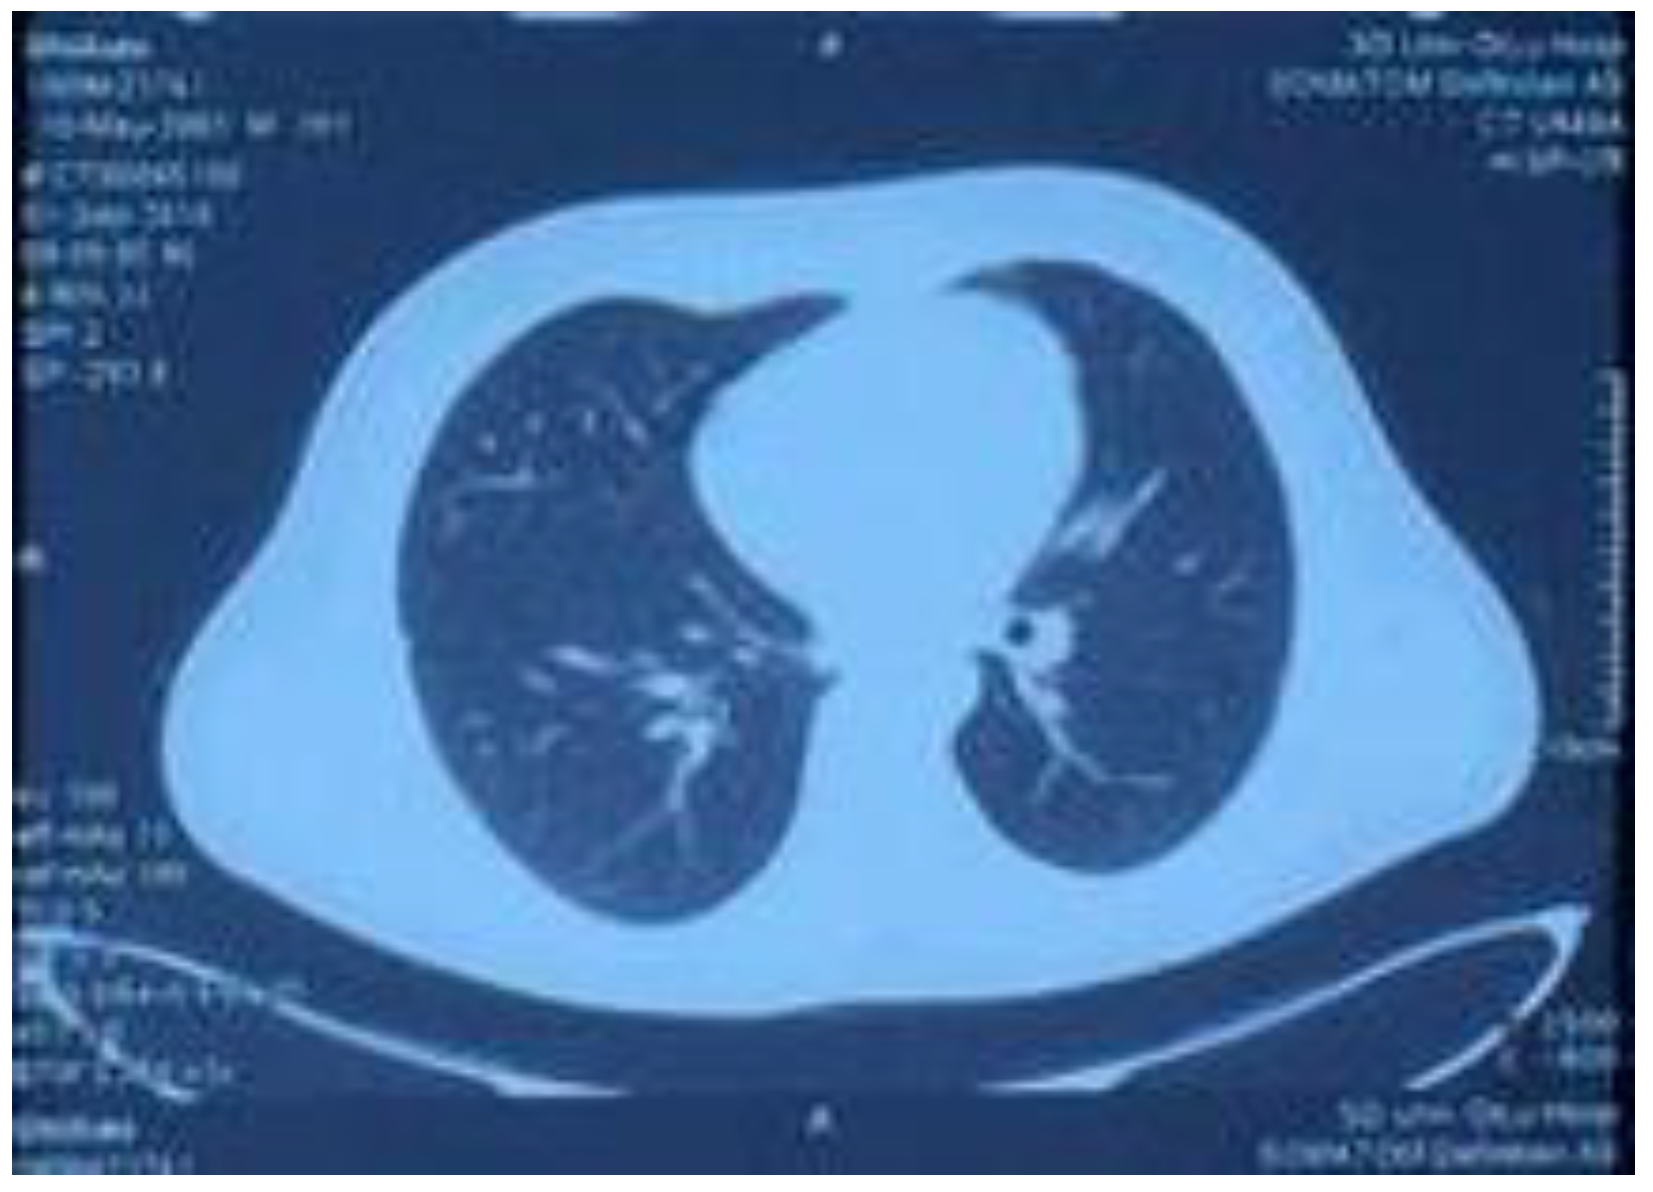

Figure 4.

Lung CT reexamination performed on 1 September 2018, showing symmetrical thorax, increased bilateral lung textures, nodules in the middle lobe of the right lung, and a small amount of high-density shadow in the lower lobe of the right lung, which was significantly smaller than before.

On 1 September, the patient came back to the hospital for routine blood examination as well as liver and kidney function and myocardial damage marker tests. The lung CT reexamination revealed that the thorax was symmetrical, the bilateral lung textures had increased, nodules were observed in the middle of the right lung, and a small amount of high-density shadow was observed in the lower right lung, which was significantly smaller than before. The examination results of the patient had normalized and reached the standard for a clinical cure. Before the submission of this paper, we made a telephone appointment with the patient; the patient was in a complete recovery state, all the examinations were normal, and he could continue to engage in various labor activities.